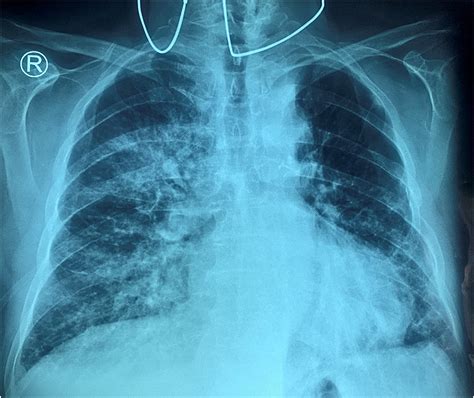

• Chest X-ray: This imaging test can reveal fluid buildup in the lungs and other abnormalities.

• pulmonary vascular congestion cxr

• pulmonary vascular congestion xray